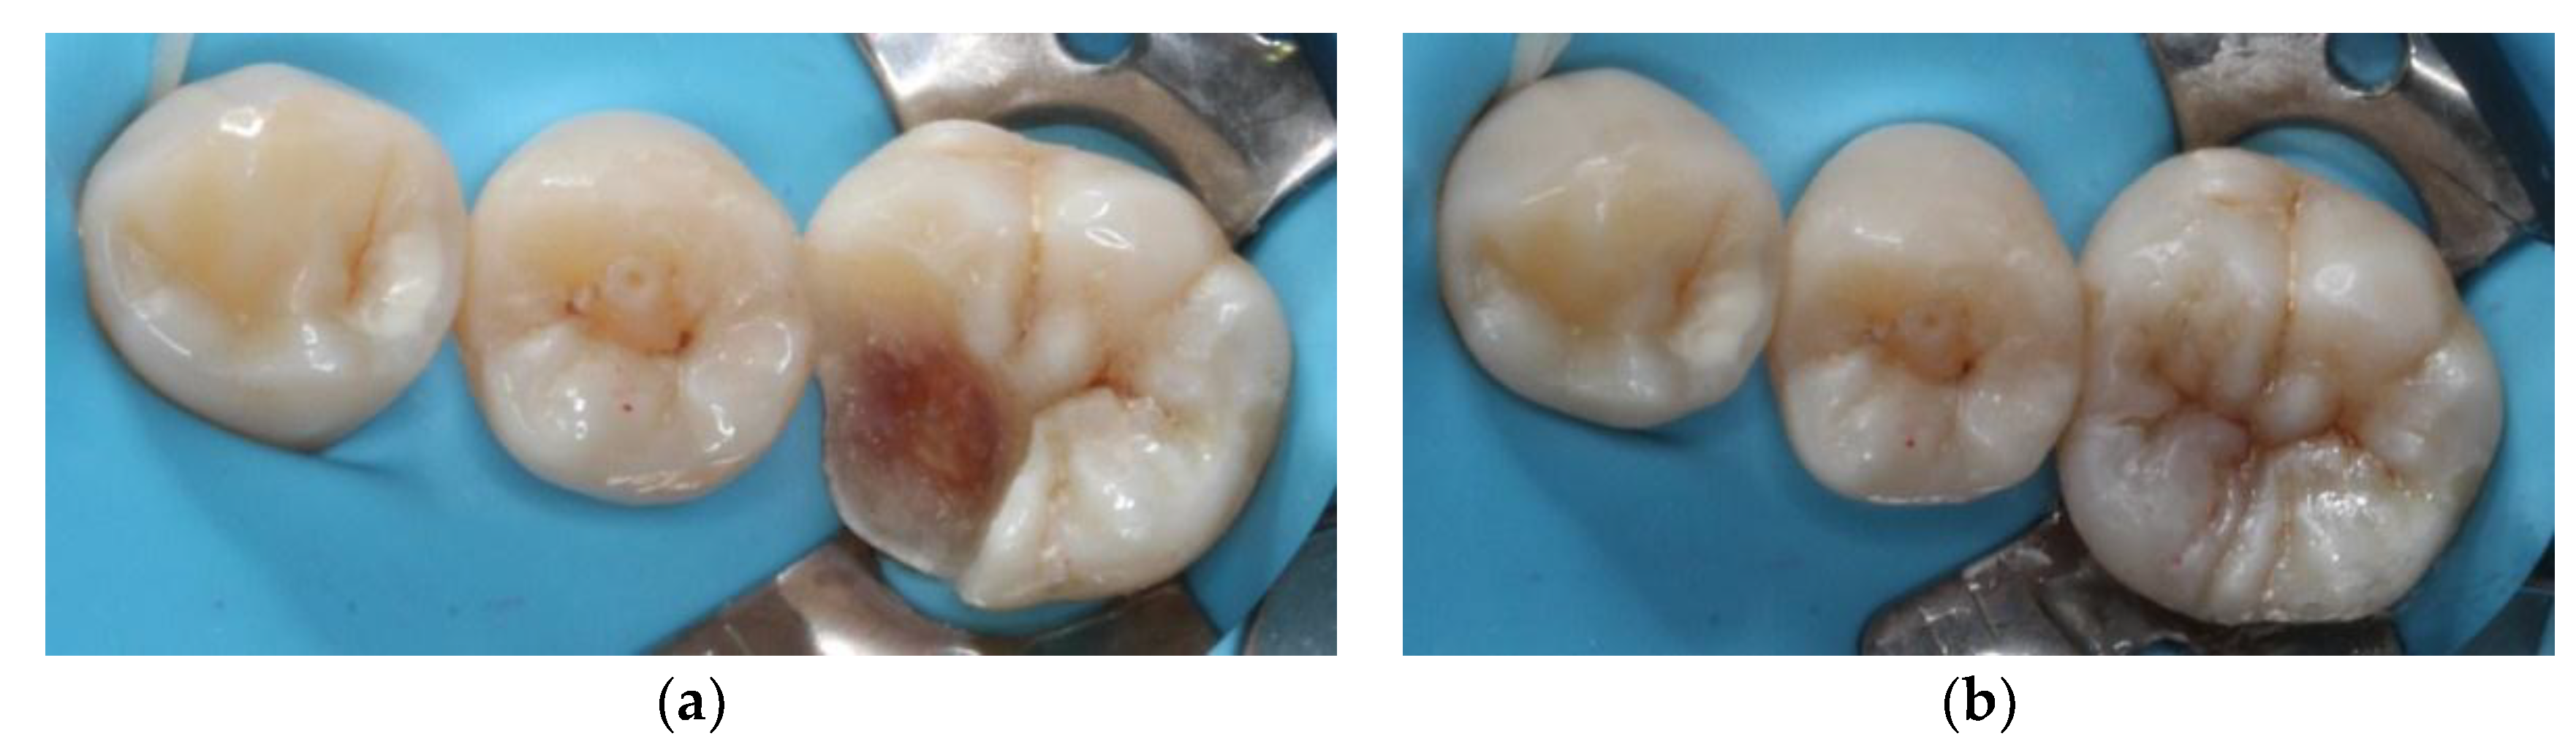

At the next appointment, isolation was performed with rubber dam. Then, the onlay was tried in and the fitness was checked. Before cementation, the intaglio surface of restoration received airborne-particle abrasion with 50 μm alumina particles; subsequently, it was conditioned with 37.5% phosphoric acid gel (Gel Etchant, Kerr, Orange, CA, USA) for 15 s. After the etchant gel was rinsed, the composite onlay was cleaned with 75% ethanol in an ultrasonic bath for 3 min. Moreover, the tooth was selectively etched with 37.5% phosphoric acid gel (Gel Etchant, Kerr, Orange, CA, USA) for 15 s, rinsed with water spray, and air dried. The self-etching adhesive and dual-cured luting composite (Multilink N system, Ivoclar Vivadent, Schaan, Liechtenstein) were used for final cementation. Polymerization was performed for 40 s per surface (

Figure 5). After rubber dam removal, the occlusal contacts were adjusted and checked with articulating paper (

Figure 6). Finally, the restoration was finished by fine-grained diamond burs and polished by abrasive, silicon-impregnated rubbers (Jiffy, Ultradent, South Jordan, UT, USA) (

Figure 7). A bitewing radiograph was taken to examine whether any overhang existed at the gingival margin (

Figure 8). At the one-year recall, the restoration still maintained its esthetic and chewing function (

Figure 9).